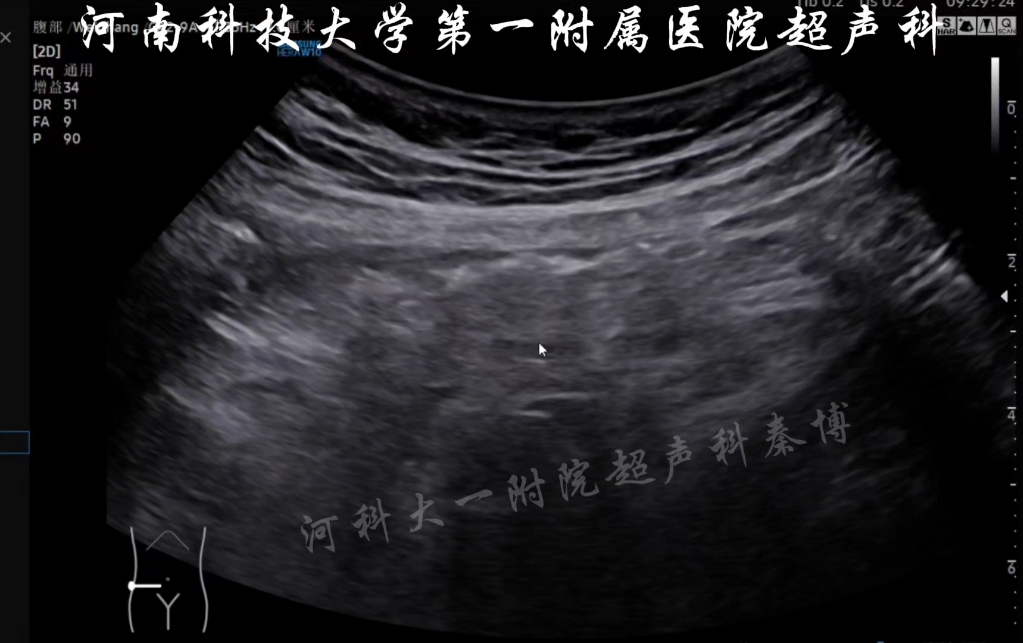

急性阑尾炎的超声模板及参考值.#超声影像典型案例 #阑尾炎

图片尺寸1080x2132